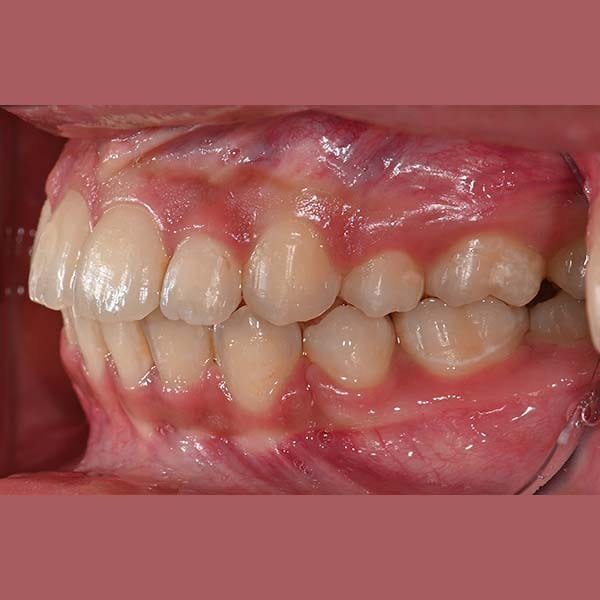

راجعتني هذه الآنسة الشابة وهي تشكو من بروز أسنانها الأمامية في كلا الفكين العلوي والسفلي، وهي حالة نسميها عادةً “البروز المضاعف”.

بعد الفحص، أكد الدكتور خالد الكاتب أن البروز كان كبيراً، وفي معظم هذه الحالات، يكون الحل الأمثل هو قلع بعض الأسنان لتوفير مسافة. وبالفعل، اعتمدت خطة العلاج على قلع الضواحك العلوية والسفلية. تم بعد ذلك استخدام تقويم الأسنان لاستغلال هذه الفراغات في إرجاع الأسنان الأمامية للخلف وتعديل ميلانها.

كما تظهر الصور، تم تصحيح البروز المضاعف بشكل كامل. تراجعت الأسنان الأمامية في كلا الفكين إلى وضعها المثالي، مما أدى إلى تحسين كبير في المظهر الجانبي للوجه وابتسامة أكثر جمالاً وتوازناً. في النهاية، بات بإمكان مراجعتنا الابتسام بثقة مجدداً.